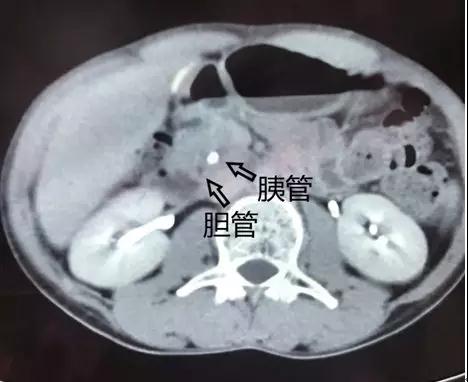

乍一看,片子上结石的位置好像是在胆管走行区域。但我盯着片子,仔细看过后发现:不是胆管结石,而是胰管结石。在胰头区域,胆管和胰管靠的很近,很容易看走眼。但正所谓“失之毫厘,谬之千里”,如果这个病人真的接受ERCP手术,按照胆管结石处理可就糟了!

我赶紧微信扎西大夫提醒他,几乎是同时,ERCP微信群里协和援藏的放射科刘炜大夫以及当地的放射科大夫也都提出了相同的意见。这是胰管结石,而且刘炜大夫还细心的在CT上画了图示进行标注。